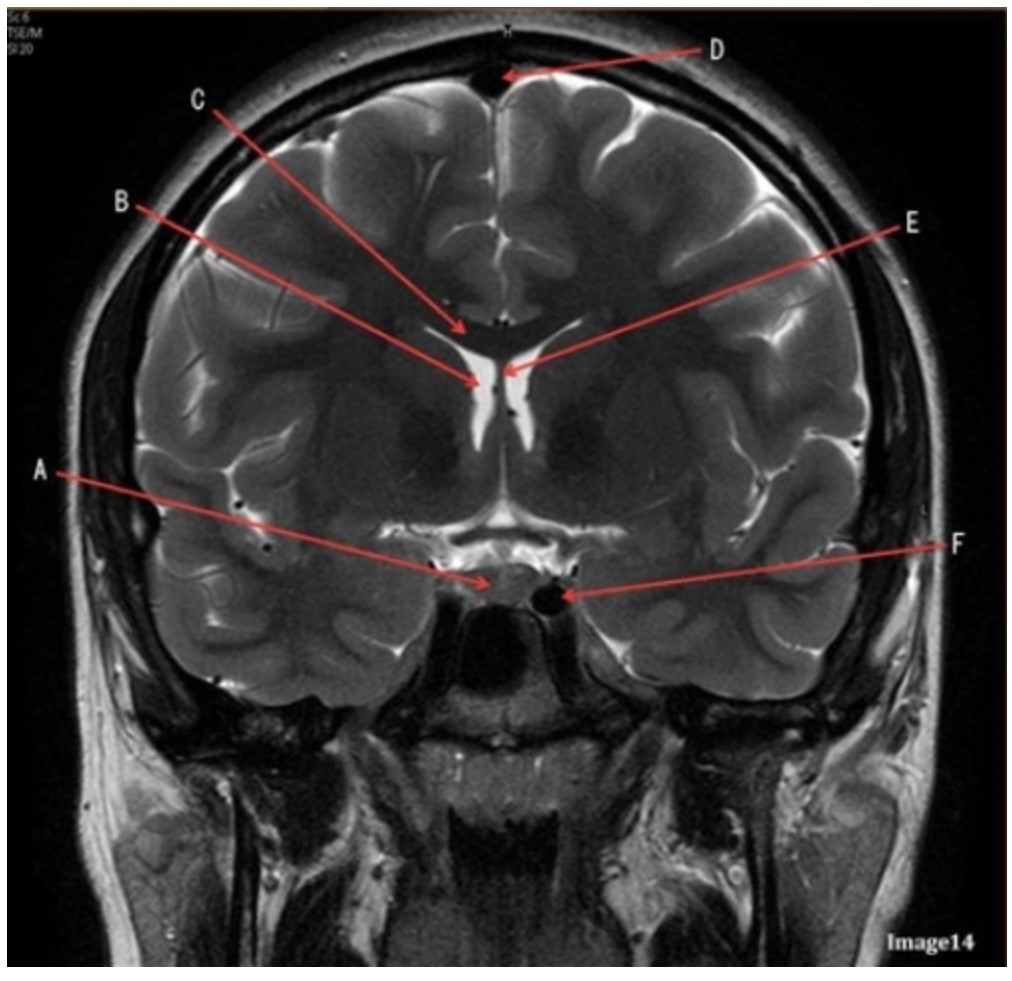

Letter F in Image 14 is pointing to:

A. Third ventricle

B. Pituitary gland

C. Hypothalamus

D. Internal carotid artery

Letter C in Image 14 is pointing to:

A. Corpus callosum

B. Third ventricle

C. Lateral ventricle

D. Pituitary gland

E. Fornix

Letter D in Image 14 is pointing to:

A. Tentorium

B. Sphenoid sinus

C. Frontal sinus

D. Sagittal sinus

E. Fornix

Letter B in Image 14 is pointing to:

A. Corpus callosum

B. Third ventricle

C. Lateral ventricle

D. Pituitary gland

E. Fornix

Letter E in Image 14 is pointing to:

A. Corpus callosum

B. Third ventricle

C. Lateral ventricle

D. Internal carotid artery

E. Fornix

Letter A in Image 14 is pointing to:

A. Corpus callosum

B. Third ventricle

C. Lateral ventricle

D. Pituitary gland

E. Fornix

Letter A in Image 14 is pointing to:

A. Corpus callosum

B. Third ventricle

C. Lateral ventricle

D. Pituitary gland

E. Fornix